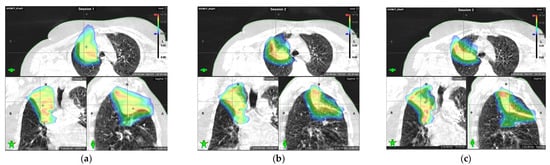

Comparison of dose distributions delivered during the first, second, and third pulses: (a) dose distribution delivered based on cone beam computed tomography (CBCT) images acquired during the first pulse; (b) dose distribution delivered based on the CBCT image acquired during the second pulse, four weeks after first pulse; (c) dose distribution delivered based on the CBCT image acquired during the third pulse, eight weeks after the first pulse. A substantial reduction in lesion size and dose to the surrounding tissue can be seen.

The reduction in target volume after the pulses (followed by pauses) resulted in a significant decrease in the dose to healthy tissue for all tissues except for the lungs. Due to tumor shrinkage, more lung tissue in the apical segment was exposed to a high dose when comparing the second and third pulse with the first one.